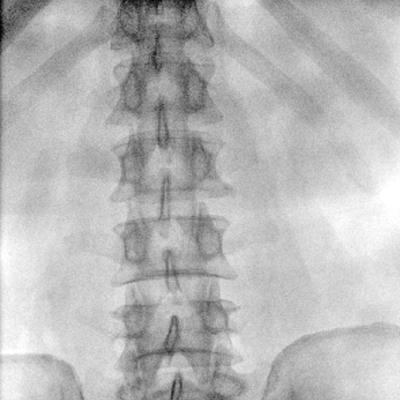

臨床適用科室:骨科、普通外科、矯形外科、創(chuàng)傷外科、泌尿外科、脊柱外科、疼痛外科、消化科、婦科等科室。

大尺寸動態(tài)平板探測器,高DQE、低噪聲、圖像清晰。采用多分辨率圖像增強(qiáng)處理技術(shù),不同部位不同圖像處理算法,滿足客戶多樣化的需求。

采用智能變頻脈沖透視技術(shù),優(yōu)化圖像質(zhì)量的同時降低輻射劑量,呵護(hù)醫(yī)患健康